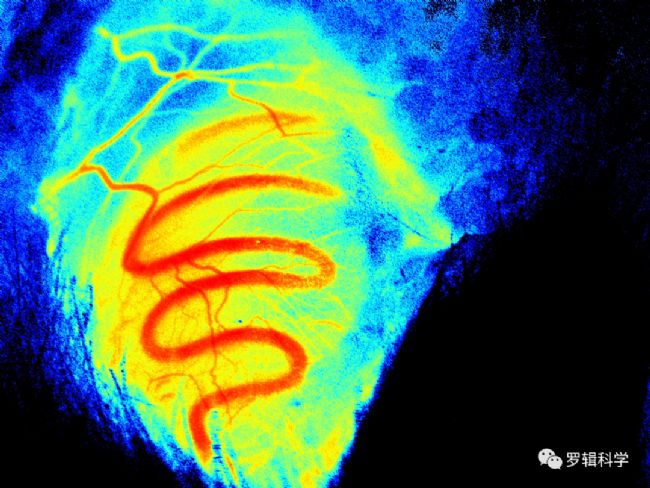

血管研究方面:超弱生物光子成像技術在體觀察評估腦缺血模型的神經元和血管活性變化,相比TTC染色和行為學測試,其可以監測腦缺血及再灌注誘導的延遲性功能性神經回路,從而評估腦缺血再灌注動物模型中的神經和血管損傷。

⼤⿏輸精管病理模型觀察

溫度降低過程⼤⿏胃內壁黏膜成像